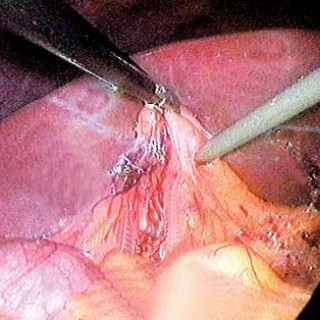

I Norge opereres ca. 6/10 000 personer årlig med kolecystektomi for gallesteinssykdom. Laparoskopisk teknikk for denne operasjonen ble innført i Norge i 1990 (1), og ble i løpet av få år standardmetode for dette inngrepet. Gallestein er vanlig. I Bergen fant Glambek og medarbeidere (2) i 1987 en prevalens på 17,7 % hos menn og 21,2 % hos kvinner, økende fra henholdsvis 4,9 % og 6,0 % i aldersgruppen 20 – 29 år til 37,0 % og 41,3 % i gruppen 60 – 69 år. Bare en firedel har behandlingstrengende symptomer: smerteanfall, galleblærebetennelse eller komplisert gallesteinssykdom...